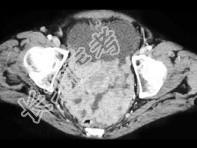

- 单项选择题55岁,女性, 结合图像,最可能的诊断是 ( )

A、卵巢癌扩散

B、结核性腹膜炎

C、胃癌

D、腹膜炎

E、以上都不是